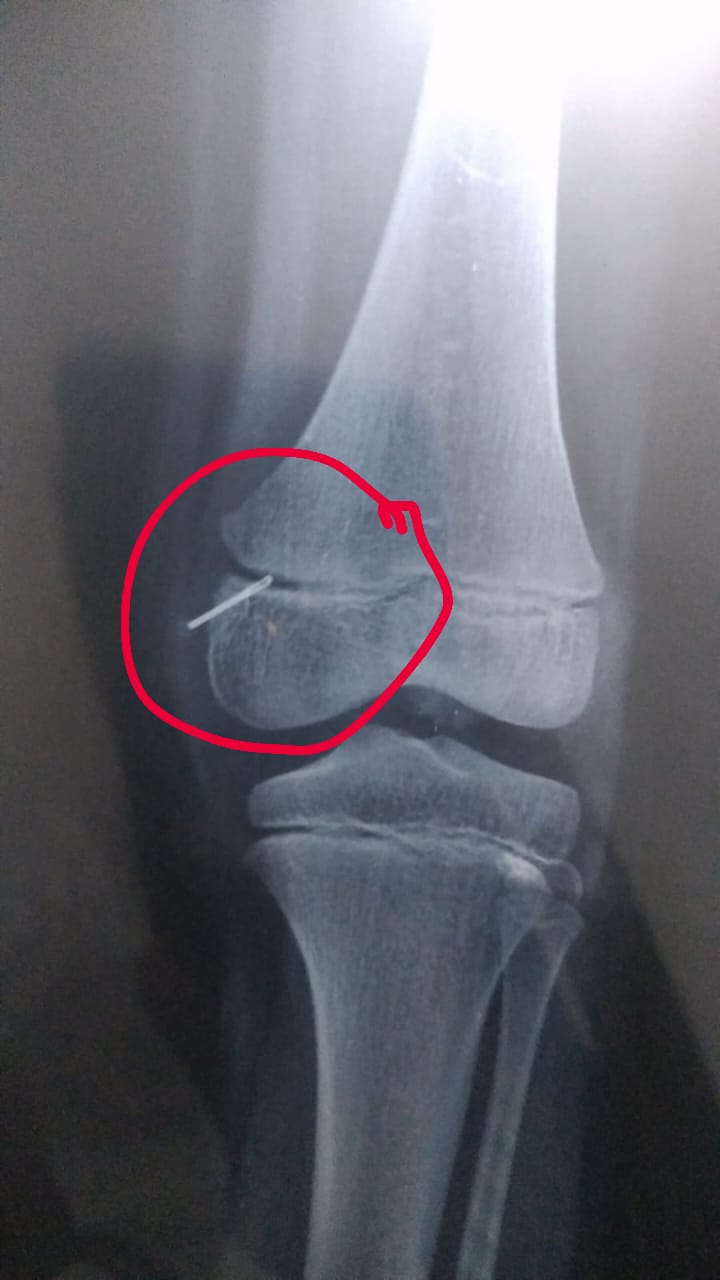

पैर की पट्टी खोलने व एक्सरे कराने के दौरान पता चलने पर अंदर से सुई निकलने पर परिजन अचंभित रह गए। पुलिस से शिकायत कर कार्रवाई की मांग की गई है।

जानकरी के अनुसार कस्बा नहटौर के मोहल्ला महकमा इमामंबड़ा में नगीना निवासी एक फर्जी चिकित्सक हड्डी जोड़ने का काम करता हैं।बताया जाता है कि एक सप्ताह पूर्व मोहल्ला दरबार सादात निवासी नाजिम के 8 वर्षीय पुत्र घर मे खेलते समय घायल हो गया था।जिसे तत्काल पैर में समस्या होने के कारण नगीना निवासी उपरोक्त डॉक्टर के यहां भर्ती कराया था।आरोप है कि चिकित्सक ने बिना जाँच किये बच्चे का उपचार शुरू कर दिया था।